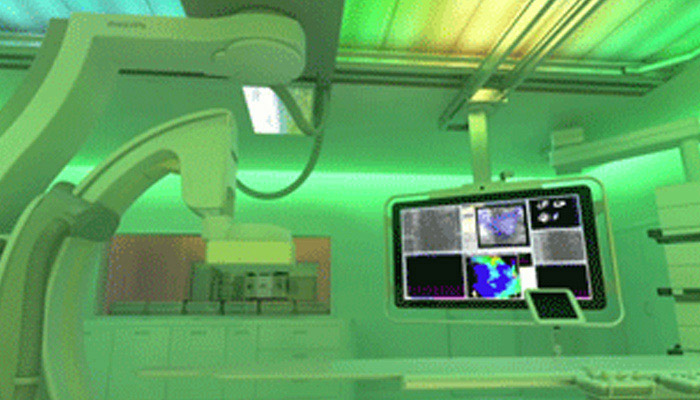

تشهد حاليًا خيارات العلاج التي لا تتطلب سوى تدخل جراحي محدود في القلب والأوعية الدموية انتشارًا ملحوظًا. ولقد ساهمت التطورات الأخيرة في مجالات التشخيص والتوجيه بالصور المباشرة Live Image Guidance والمعلوماتية في جعل هذا الأمر ممكنًا. بالتعاون مع أشهر أطباء أمراض القلب، ابتكرنا حلولاً تساهم في منح المرضى الفرصة لتغيير حياتهم. فهذه الحلول تساعد في تسريع سير العمل وزيادة فعالية الطاقم الطبي وتوفير أفكار سريرية.

معًا، سنغير طريقة تقديم الرعاية وسنحسّن نوعية حياة مرضى القلب والأوعية الدموية.